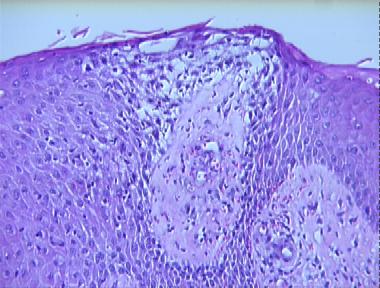

stasis dermatitis

Histologic Features